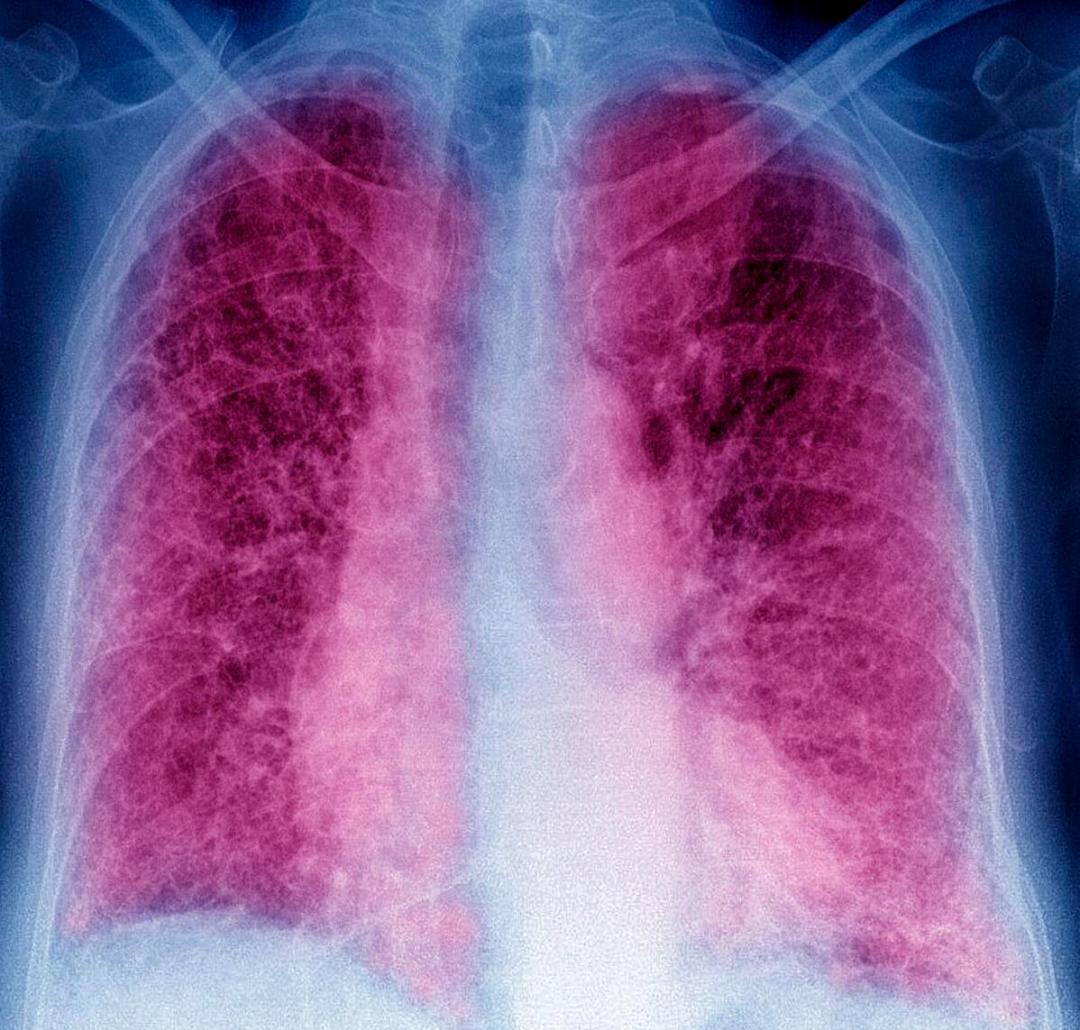

晚期肺癌是一种全身性疾病。此时,肺癌和肺癌转移灶在患者全身有两个甚至更多的器官。此时,即使多个部门联合起来,所有的肿瘤疾病都被切除,肺癌也无法治愈。化疗、放疗、靶向、免疫疗法等所有保守疗法都无法治愈。这是因为什么。

问题出在肺癌细胞本身。昨天直播期间,一个朋友讲述了他肺癌患者的病程。患者确诊肺癌14年,术后复发,口服靶向药物后耐药。直到最近,他才发现自己的转移炉一直在稳步增加。穿刺后,他发现腺癌的疾病已经变成了小细胞肺癌。这个病例被认为是一个非常成功的癌症预防,但仍然无法避免耐药的最终结果。归根结底,癌细胞一直在变化。

如今,治疗最成功的癌症是血液肿瘤中的急性早期颗粒性白血病。经过维甲酸治疗,恶化的白细胞自行凋亡,癌症甚至可以缓解20多年,适当变成慢性病。目前肺癌的治疗思路还是以消灭为主,没有诱导凋亡的治疗方法。然而,所有的消灭药物最终都会因癌细胞突变而失去原有的目标。所以肺癌不能根治的原因还是癌细胞本身。